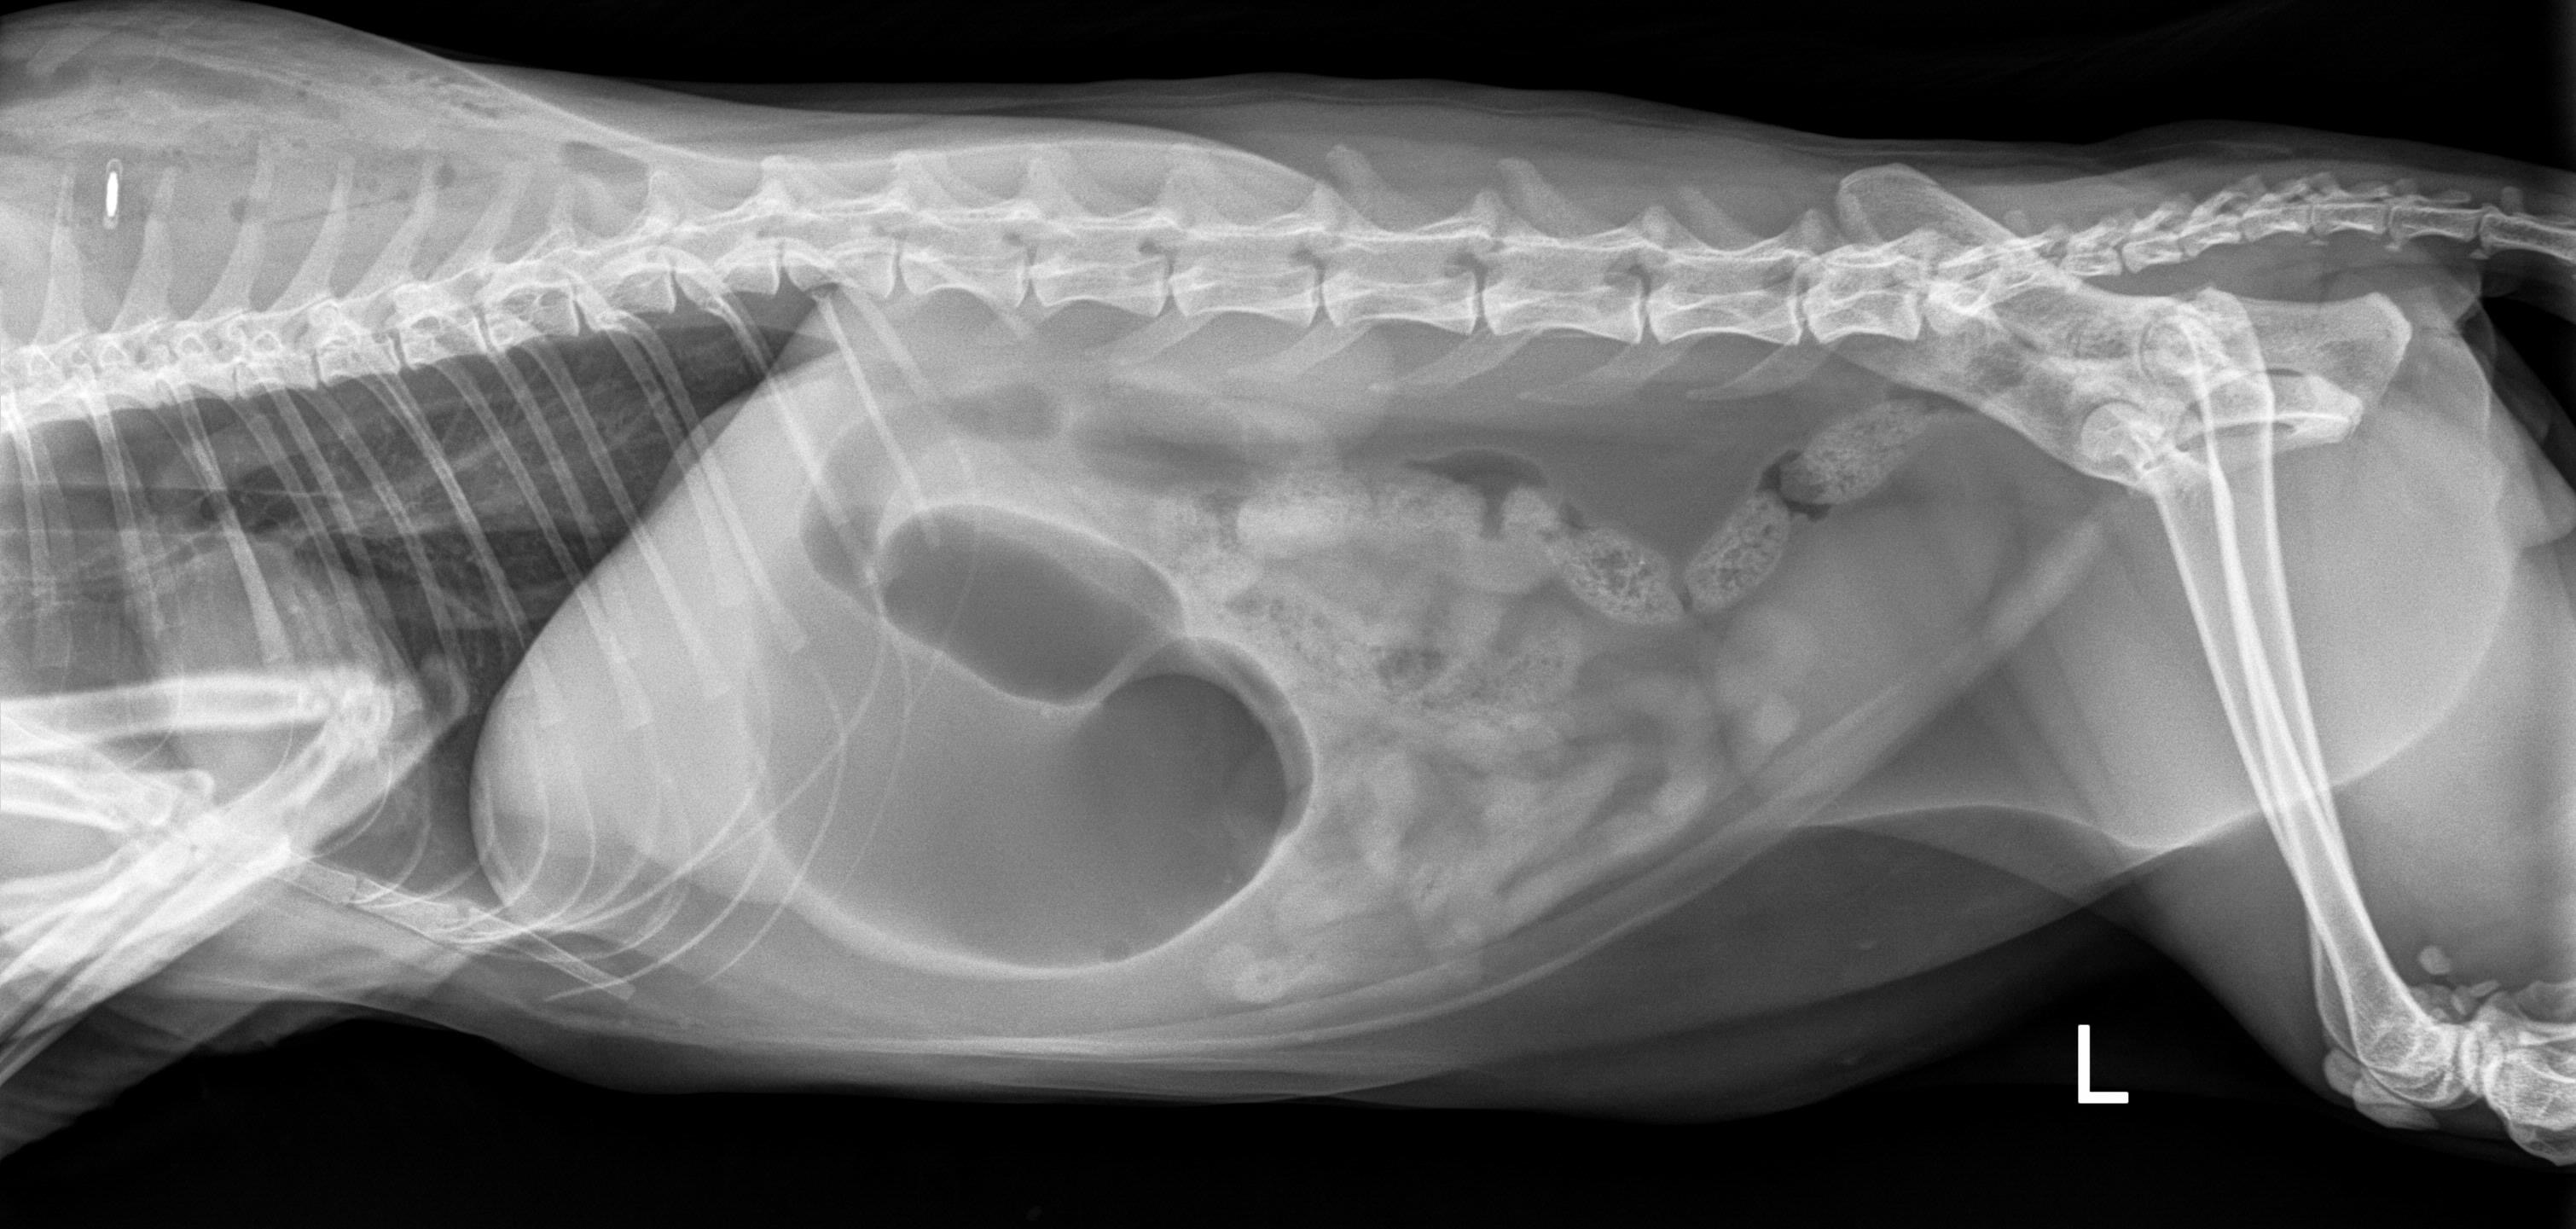

Thursday 3/19 Pocket began to act off at home, he was howling and going in and out of the litter box, then the vomiting started. Being a previous urinary cat he was taken right in to the vet to make sure he was not “blocked” or trying to block.. turned out he was not but remained at the vet to be able to gain a urine sample. Friday 3/20 the sample showed an infection.. medication prescribed and home he went. Over the weekend he was listless and did not eat or drink, by Sunday 3/22 he was cold, nose and gums white and extremely lethargic. Back to the vet he went on Monday 3/23 and bloodwork was run, showing up pancreatitis! New meds on board, fluids given, home he went. Still not eating at all. Poor guy looks awful and painful.. Returned for repeat fluids today 3/24, then vomiting began again, projectile vomiting, X-ray performed and the stomach was so bloated, unable to tell if there was gastric torsion or a foreign body happening? Truthfully the only option now, exploratory surgery. The unexpected bill already high, and adding surgery, but Pocket is 3 &1/2 years old and deserved the chance..

Surgery performed, foreign body located and removed!! If your children play hockey you would be familiar with “knee” hockey balls.. in this house all the animals play hockey with our boy.. the dogs like to chew the balls, apparently Pocket thought a piece looked appetizing.. let this be a lesson.. make sure you throw out all pieces of any damaged toys that pets may find delicious!